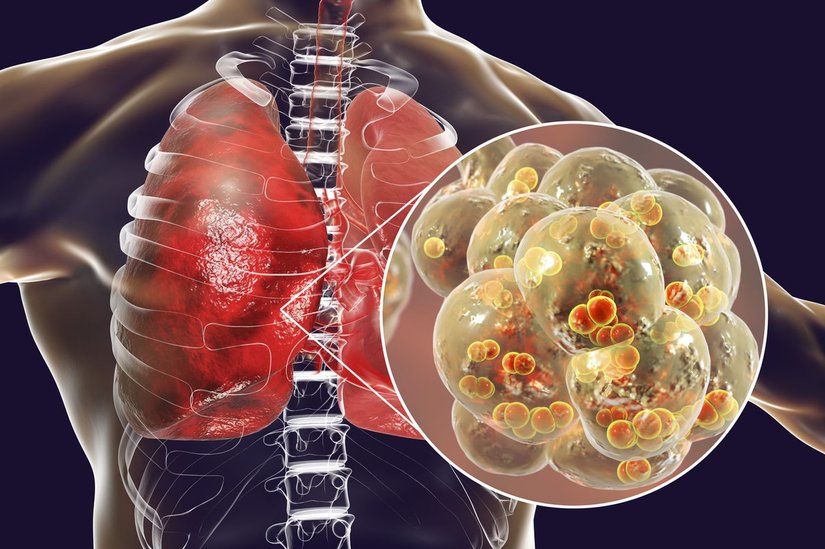

Zatürre, alveoller adı verilen akciğer keseciklerini etkileyen bir iltihaplanmadır. Bu bakımdan, akciğer iltihabının ("pnömotit" hastalığının) bir versiyonu olduğu söylenebilir.

Zatürre, genellikle üst solunum yollarında başladıktan sonra kademeli olarak alt solunum yollarına iner. Akciğerlere ulaşan bakteriler, hücreler ve alveoller arasındaki boşluklarda çoğalmaya başlar. Burada savunma sistemine ait makrofajlar ve nötrofiller, bu yabancı bakterileri yok etmeye çalışır. Nötrofiller tarafından salgılanan sitokinler, genel savunma sistemi tepkisini tetikler.

Buna bağlı olarak ateş çıkar, soğuk titremeler yaşanır ve bakteriyel zatürrede yaygın olarak görülen bitkinlik oluşur. Bakteriler, nötrofiller ve civardaki kan damarlarından sızan sıvılar, zatürreye ait tipik göğüs X-ışını taraması fotoğraflarındaki bulutlu görünüme neden olur:

Virüsler de benzer şekilde, kontamine olmuş cisimlere dokunma ve sonrasında ağız, burun ve gözlere dokunma yoluyla vücuda giriş yapar. Zatürre virüsleri ayrıca hapşırık ve öksürük sırasında oluşan damlacıklar yoluyla da insandan insana geçiş yapabilmektedir. Üst solunum yollarına ulaşan virüs, kısa sürede akciğerlere inerek buradaki keseleri ve akciğer parankimasını işgal etmeye başlar. Bazı virüsler kan yoluyla da akciğerlere ulaşabilir.

Bu viral enfeksiyon nedeniyle akciğer dokusu yavaş yavaş ölmeye başlar. Savunma sisteminin tepkisi, virüsü öldürmek yerine daha fazla akciğer hasarına neden olabilir. Ayrıca viral zatürreye sebep olan virüsler, akciğer-harici organlara da sıçrayarak buralarda da tahribata neden olabilirler.